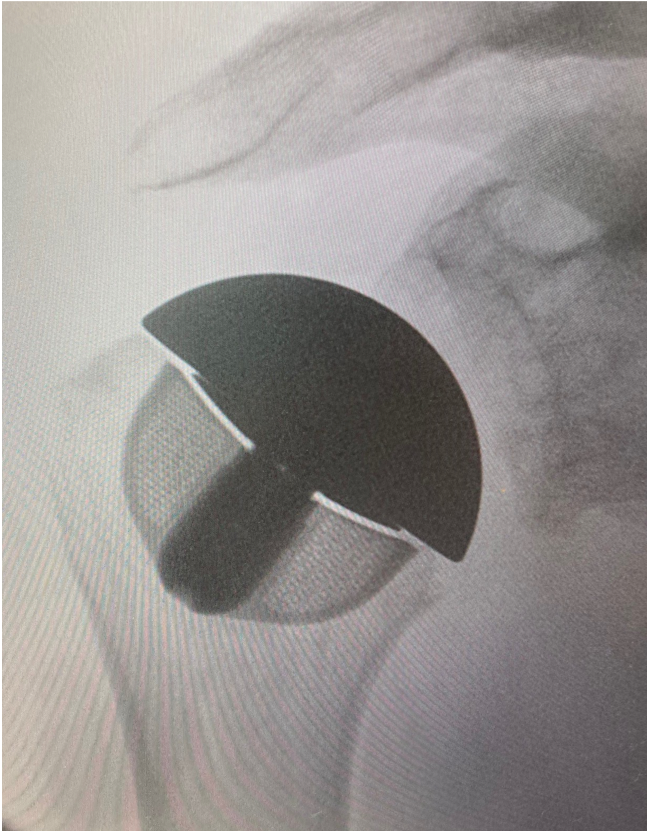

Post-op

Implantation of LINK Embrace using

- Stemless Cage Size 36

- Neutral Head Adapter

- Humeral Head with 44 mm diameter, 18 mm height

- Cemented All-Poly Glenoid Size M

- Very good reconstruction of joint morphology and kinematics

- Well balanced soft tissue tension

- Good ROM and stability